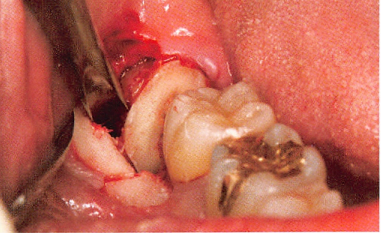

临床分为3期:Ⅰ期有死骨出现但无明显临床症状;Ⅱ期病变局限在牙槽骨内,死骨暴露,并有红肿疼痛等感染症状,伴或不伴口内瘘管;Ⅲ期病变超出牙槽骨范围出现死骨,伴疼痛、感染,并至少伴有病理性骨折、口外瘘管、下颌骨下缘或鼻窦底部骨质溶解破坏3 项之一。

根据此标准,BONJ 的诊断并不困难。目前,BONJ 的发生机制尚不清楚,有人认为可能与BP 药物抑制破骨细胞功能、诱导凋亡、微血管栓塞、创伤和感染等因素有关。结合相关文献,BONJ 静脉和口服药物的发病率分别约为1%和0. 002%。目前,BONJ 尚缺乏理想的治疗方法,临床上主要使用刮除死骨、冲洗创面,高压氧等方法治疗。但是疗效并不确切,有相当大比例的患者病情迁延不愈,因此BONJ 重在预防。